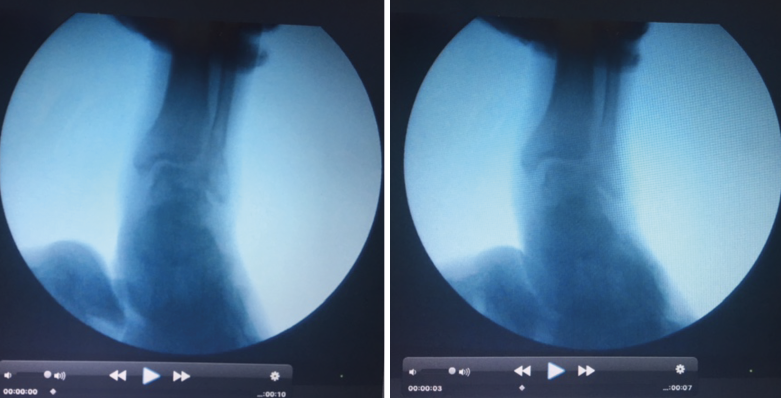

• Pruebas complementarias dinámicas/intraoperatorias:

– Radiología de estrés:

- Test en valgo y rotación externa, valorando el aumento del espacio claro medial (> 5 mm) (Figura 7).

- Hook test: aumento > 2 mm al traccionar del peroné en sentido mediolateral.

La valoración más fiable y que descarta variaciones morfológicas es la que se realiza comparando los parámetros radiológicos a estudio entre la radiología intraoperatoria del tobillo afecto respecto a la del tobillo sano.

Figura 7. Pruebas complementarias dinámicas/intraoperatorias para el estudio de la sindesmosis. Radiología de estrés bajo control radiológico. El test en valgo y la rotación externa ponen de manifiesto el aumento del espacio claro medial (> 5 mm).